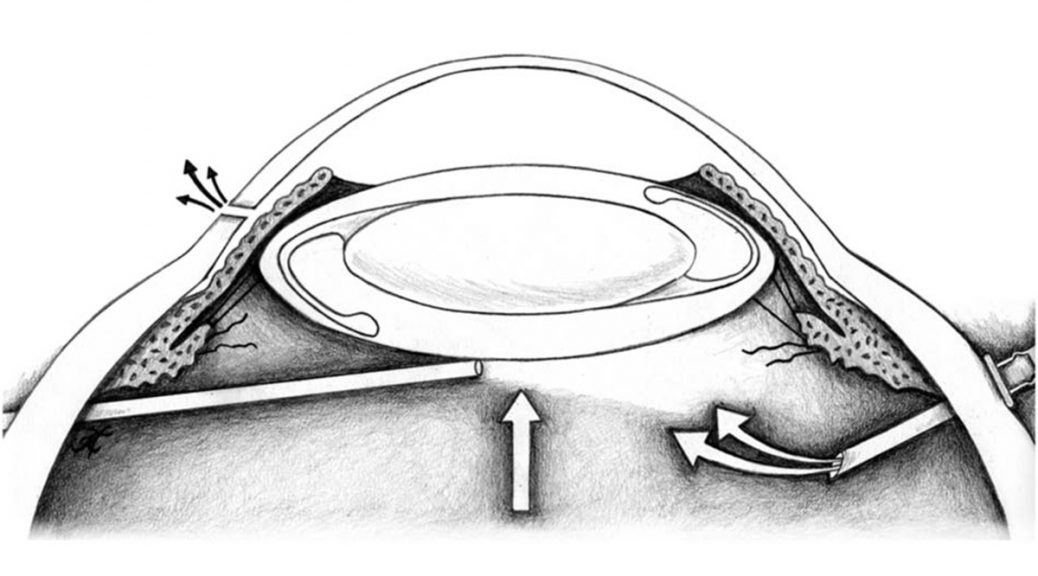

This publication is not the first to feature Kathy May’s medical knowledge but it is the first to feature her medical illustration! Take a look at this surgical technique paper by the one and only Ken Wald, written along with Joe Tseng, Jane Myung, and Alex Dillon that was published in Retina, the premier scientific publication for retina specialists. The paper describes a technique for managing the dislocation of an intraocular lens implant along with its surrounding capsule occurring at some point after previous cataract surgery. The whole lens-capsule complex is sutured to the back of the iris while being held in place from behind by tools and fluid infusion. This technique allows the surgeon to secure the lens implant back in place while minimizing manipulation of the lens and avoiding the need to remove and replace it with a new lens.

Click here to read the paper! Kathy May first drew the illustrations in pencil and colored pencil (first image below), then scanned them and cleaned them up in Photoshop (2nd, 3rd, and 4th images below):